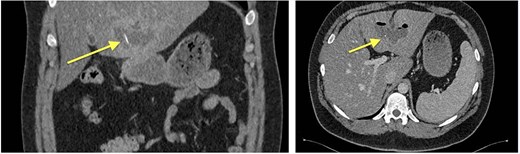

Eventually, diagnostic laparoscopy showed a small posterior gastric perforation next to the liver abscess with migration of the metal bristle into the liver, causing the abscess. Consecutively, surgical drainage of liver abscess, recovery of the foreign body, and gastric perforation repair with sutures were performed (Fig. 4). No postoperative complications occurred. The patient received intravenous antibiotic treatment for 10 days, followed by oral antibiotics for another 4 days. Follow-up showed decreasing CRP and WBC and rapid recovery after surgery. On the 4th postoperative day, the patient could be discharged.